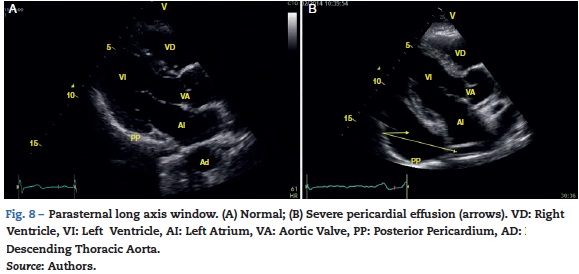

Cardiac tamponade

Pericardial effusion is identified as a hypoechoic image between the hyperechoic pericardial blades (Fig. 8) and later it is determined whether it contributes to the patient's instability. As cardiac tamponade is produced when the pressure inside the pericardium impedes filling during the relaxation phase, diastolic collapse should be searched for initially in the right cavities since they have lower pressure (Fig. 9).24,51 The spectrum of presentation of the tamponade can range from an inward deviation of the atrium to a complete compression of the chamber in diastole.51 In addition, a distended inferior vena cava can be seen as part of the diagnosis.24